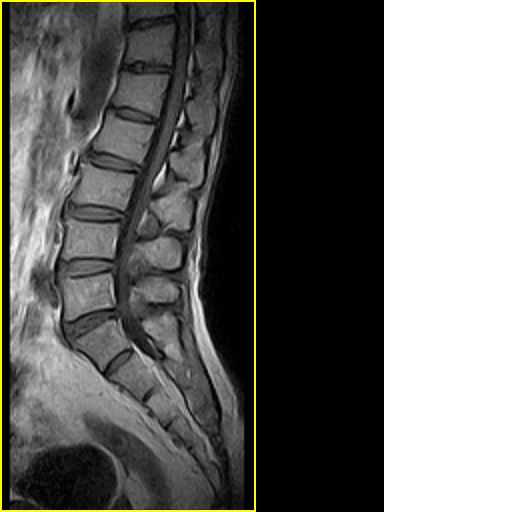

标题: MRI0859:[原创]腰椎,男,78岁,右下肢跛行两月 [打印本页]

男,78岁,右下肢跛行两月.

右侧黄韧带肥厚或钙化,压迫马尾神经所致。必要时行ct扫描。

腰间盘膨出、黄韧带肥厚、可疑先天性腰椎管狭窄。

退行性骨关节病:增生、椎间盘变性、膨出...

退行性病变:增生、椎间盘变性、膨出[l4-5、l5-s1 椎间盘膨出]

退行性骨关节病:增生、椎间盘变性、膨出..黄韧带肥厚.

黄韧带肥厚.